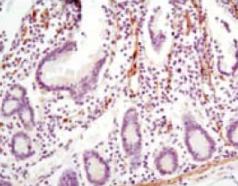

IHC    1/200 - 1/1000